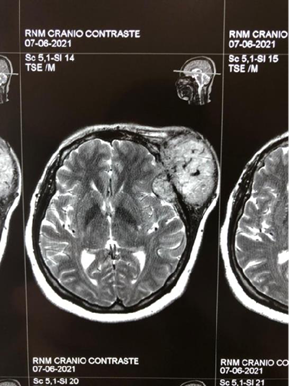

Figure 3A Contrast-enhanced magnetic resonance image showing a tumor in the extraaxial region of left frontal involvement

Figure 3B Contrast-enhanced magnetic resonance imaging showing a tumor in the extraaxial region of left frontal involvement in coronal section.